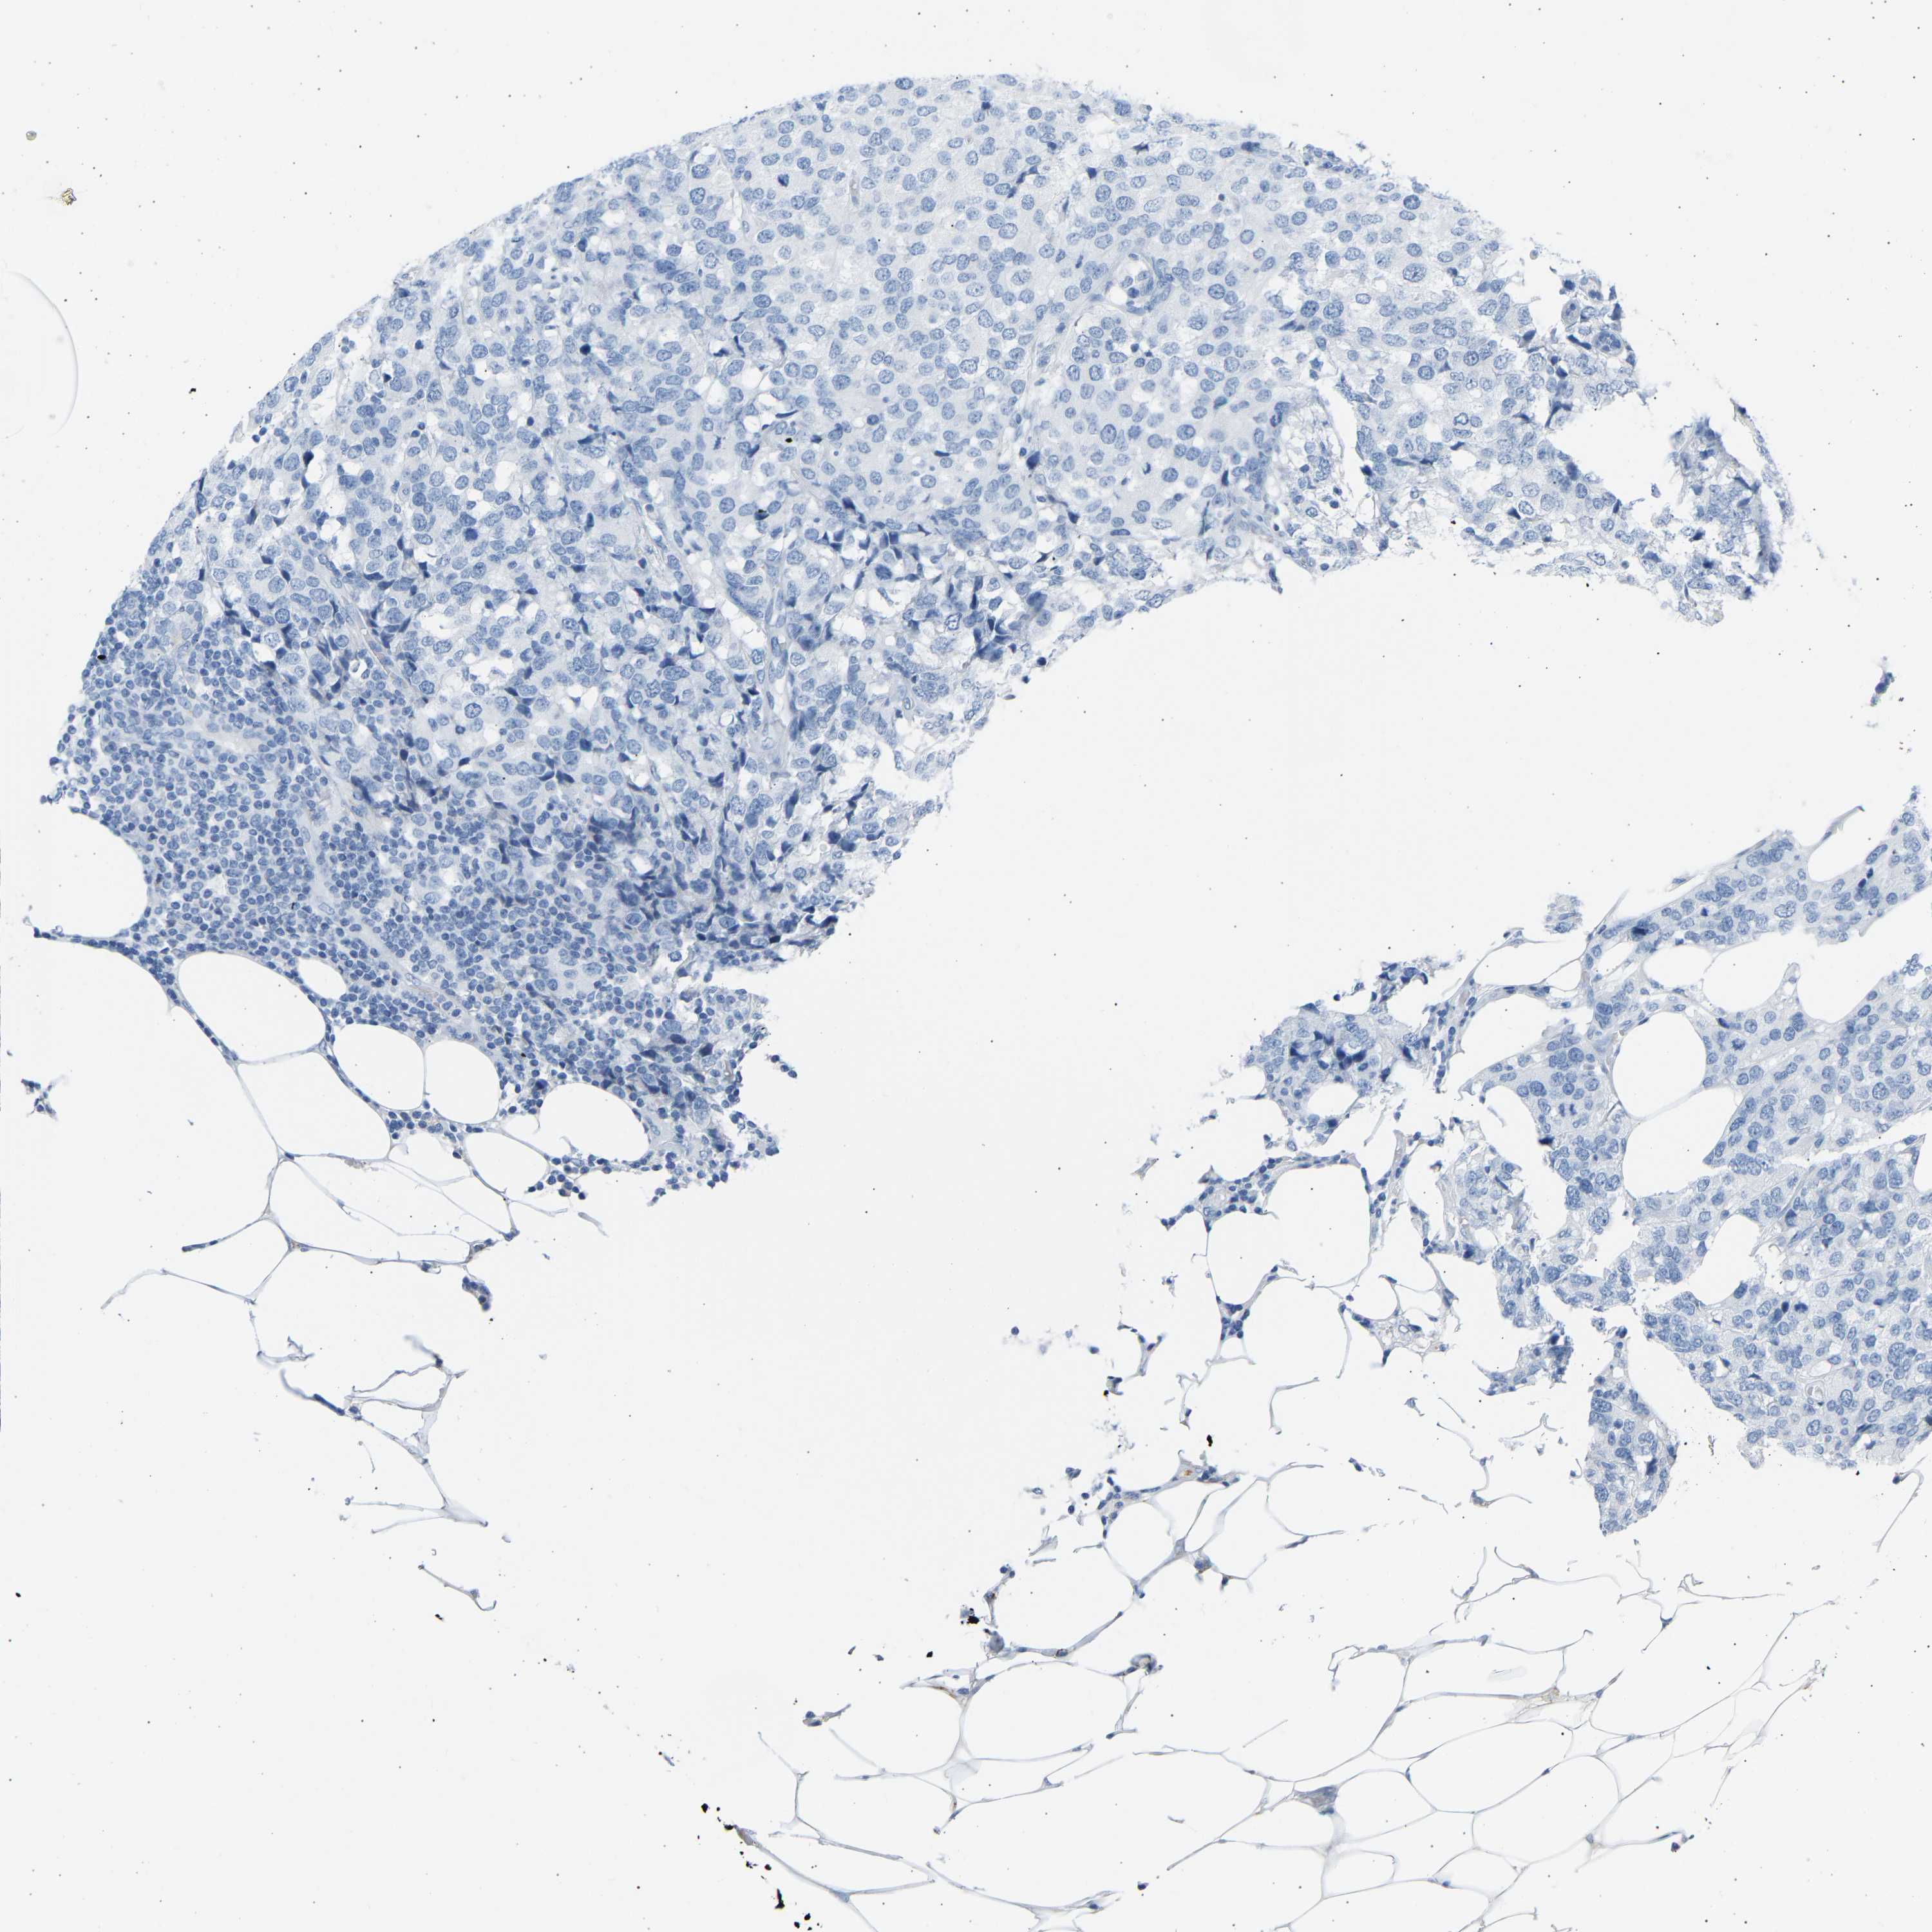

BRCA TCGA BRCA VALIDATION PROTEIN EXPRESSION

ANTIBODIES

AND

VALIDATION